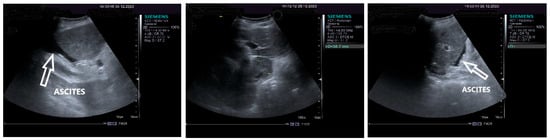

The pulsed Doppler ultrasound revealed a patency of the main portal vein as well as of the left and right portal branches and decreased, demodulated hepatopetal portal venous flow, with mildly decreased respiratory variability in the amplitude of the portal vein flow. The Dopler aspects of the liver and spleen are illustrated in Figure 4.

The measurements of the resistivity index of the hepatic artery at the liver hilum revealed increased values (HARI = 0.79). However, the liver elastography demonstrated a low stiffness. The measurements were made using the acoustic radiation force impulse (ARF)I method, by point shear wave (p SWE) elastography, and the obtained median value was 1.24 m/s, IQR = 0.12, equivalent to an F2 Metavir fibrosis score. Therefore, the diagnosis of liver cirrhosis was highly improbable. The elastography of the right liver lobe performed by the ARFI method, pSWE, is presented in Figure 5.

Figure 4. Doppler examination. Liver: pulsed Doppler of the portal vein (left). Spleen: color Doppler of splenic vein (right).